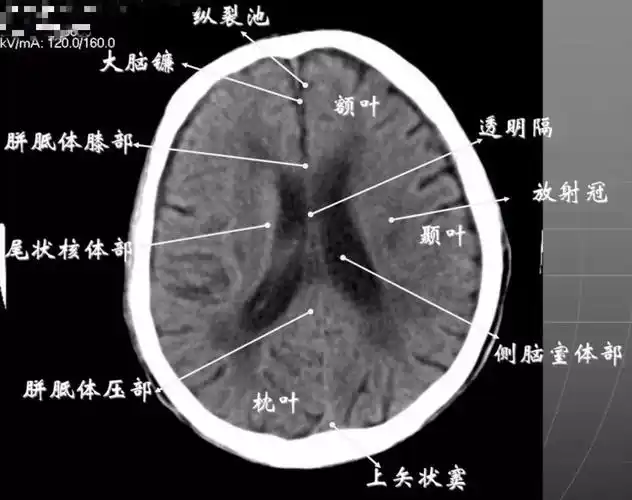

头颅ct 解剖图谱,人手一份